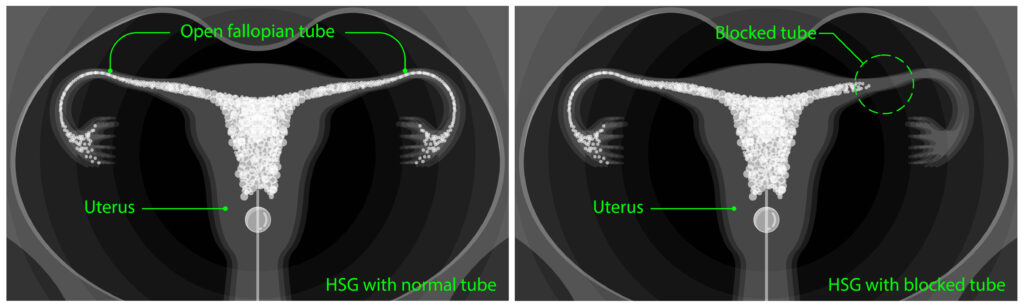

Then, a contrast liquid is inserted through the catheter and an X-ray is of the uterus is taken to detect the blockage. Then, the doctor will insert a second catheter to remove the blockage.